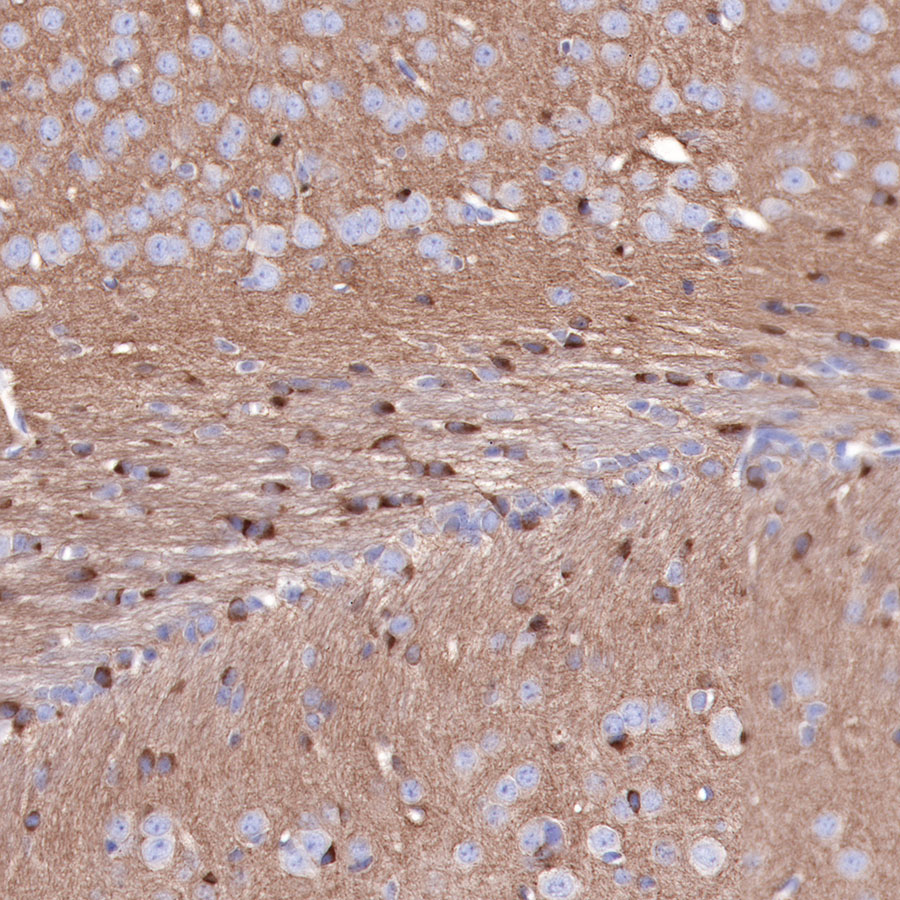

IHC shows positive staining in paraffin-embedded mouse cerebral cortex. Anti-Tau antibody was used at 1/2000 dilution, followed by a HRP Polymer for Mouse & Rabbit IgG (ready to use). Counterstained with hematoxylin. Heat mediated antigen retrieval with Tris/EDTA buffer pH9.0 was performed before commencing with IHC staining protocol.